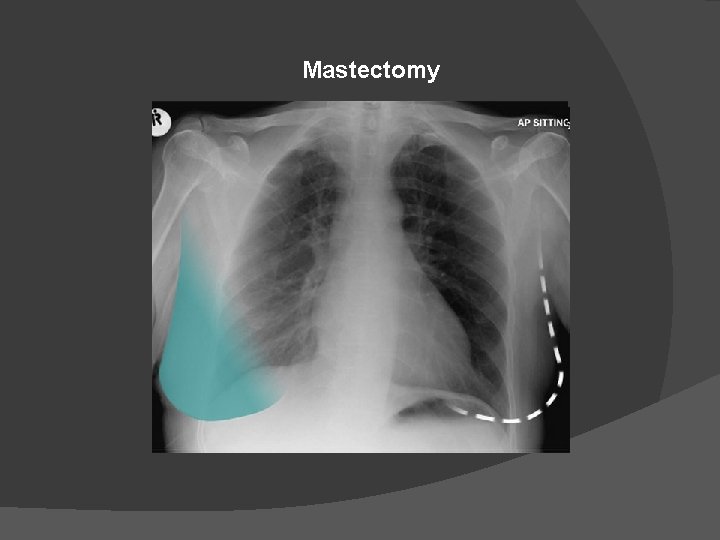

Mastectomy